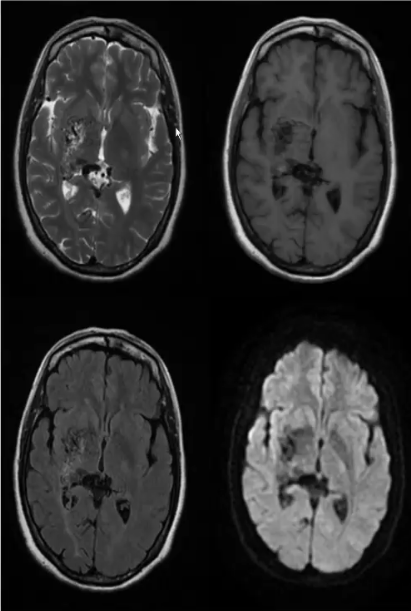

血管畸形

❖ 颅内的血管畸形可分为动静脉畸形(AVM)、海绵状血管瘤、毛细血管扩张症、静脉血管瘤或静脉发育异常四种病理类型。

❖ 任何类型的血管畸形均可发生于丘脑。